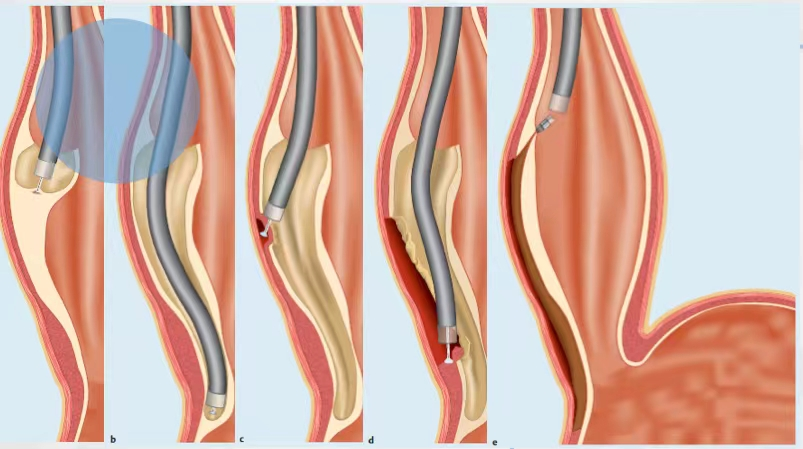

POEM—不开刀治疗贲门失弛缓症

贲门失驰缓症是一种非常罕见的疾病,年发病率为每10万人1例,每10万人患病率为10例。它是一种由食管胃交界部神经肌肉功能障碍导致的功能性疾病,患者常常会有吞咽困难、胸痛、体重减轻的症状,甚至因为返流误吸反复发生肺炎、生活质量差。

POEM,即经口内镜下肌切开术,是一种通过隧道内镜技术进行肌切开的内镜微创新技术,这种技术治疗贲门失驰缓症相比较于开胸手术或胸腔镜手术有诸多优势,已成为贲门失驰缓症的首选治疗方法。全部手术过程均在无痛状态下通过胃镜进行操作,手术时间短、创伤小,患者恢复快,疗效可靠。